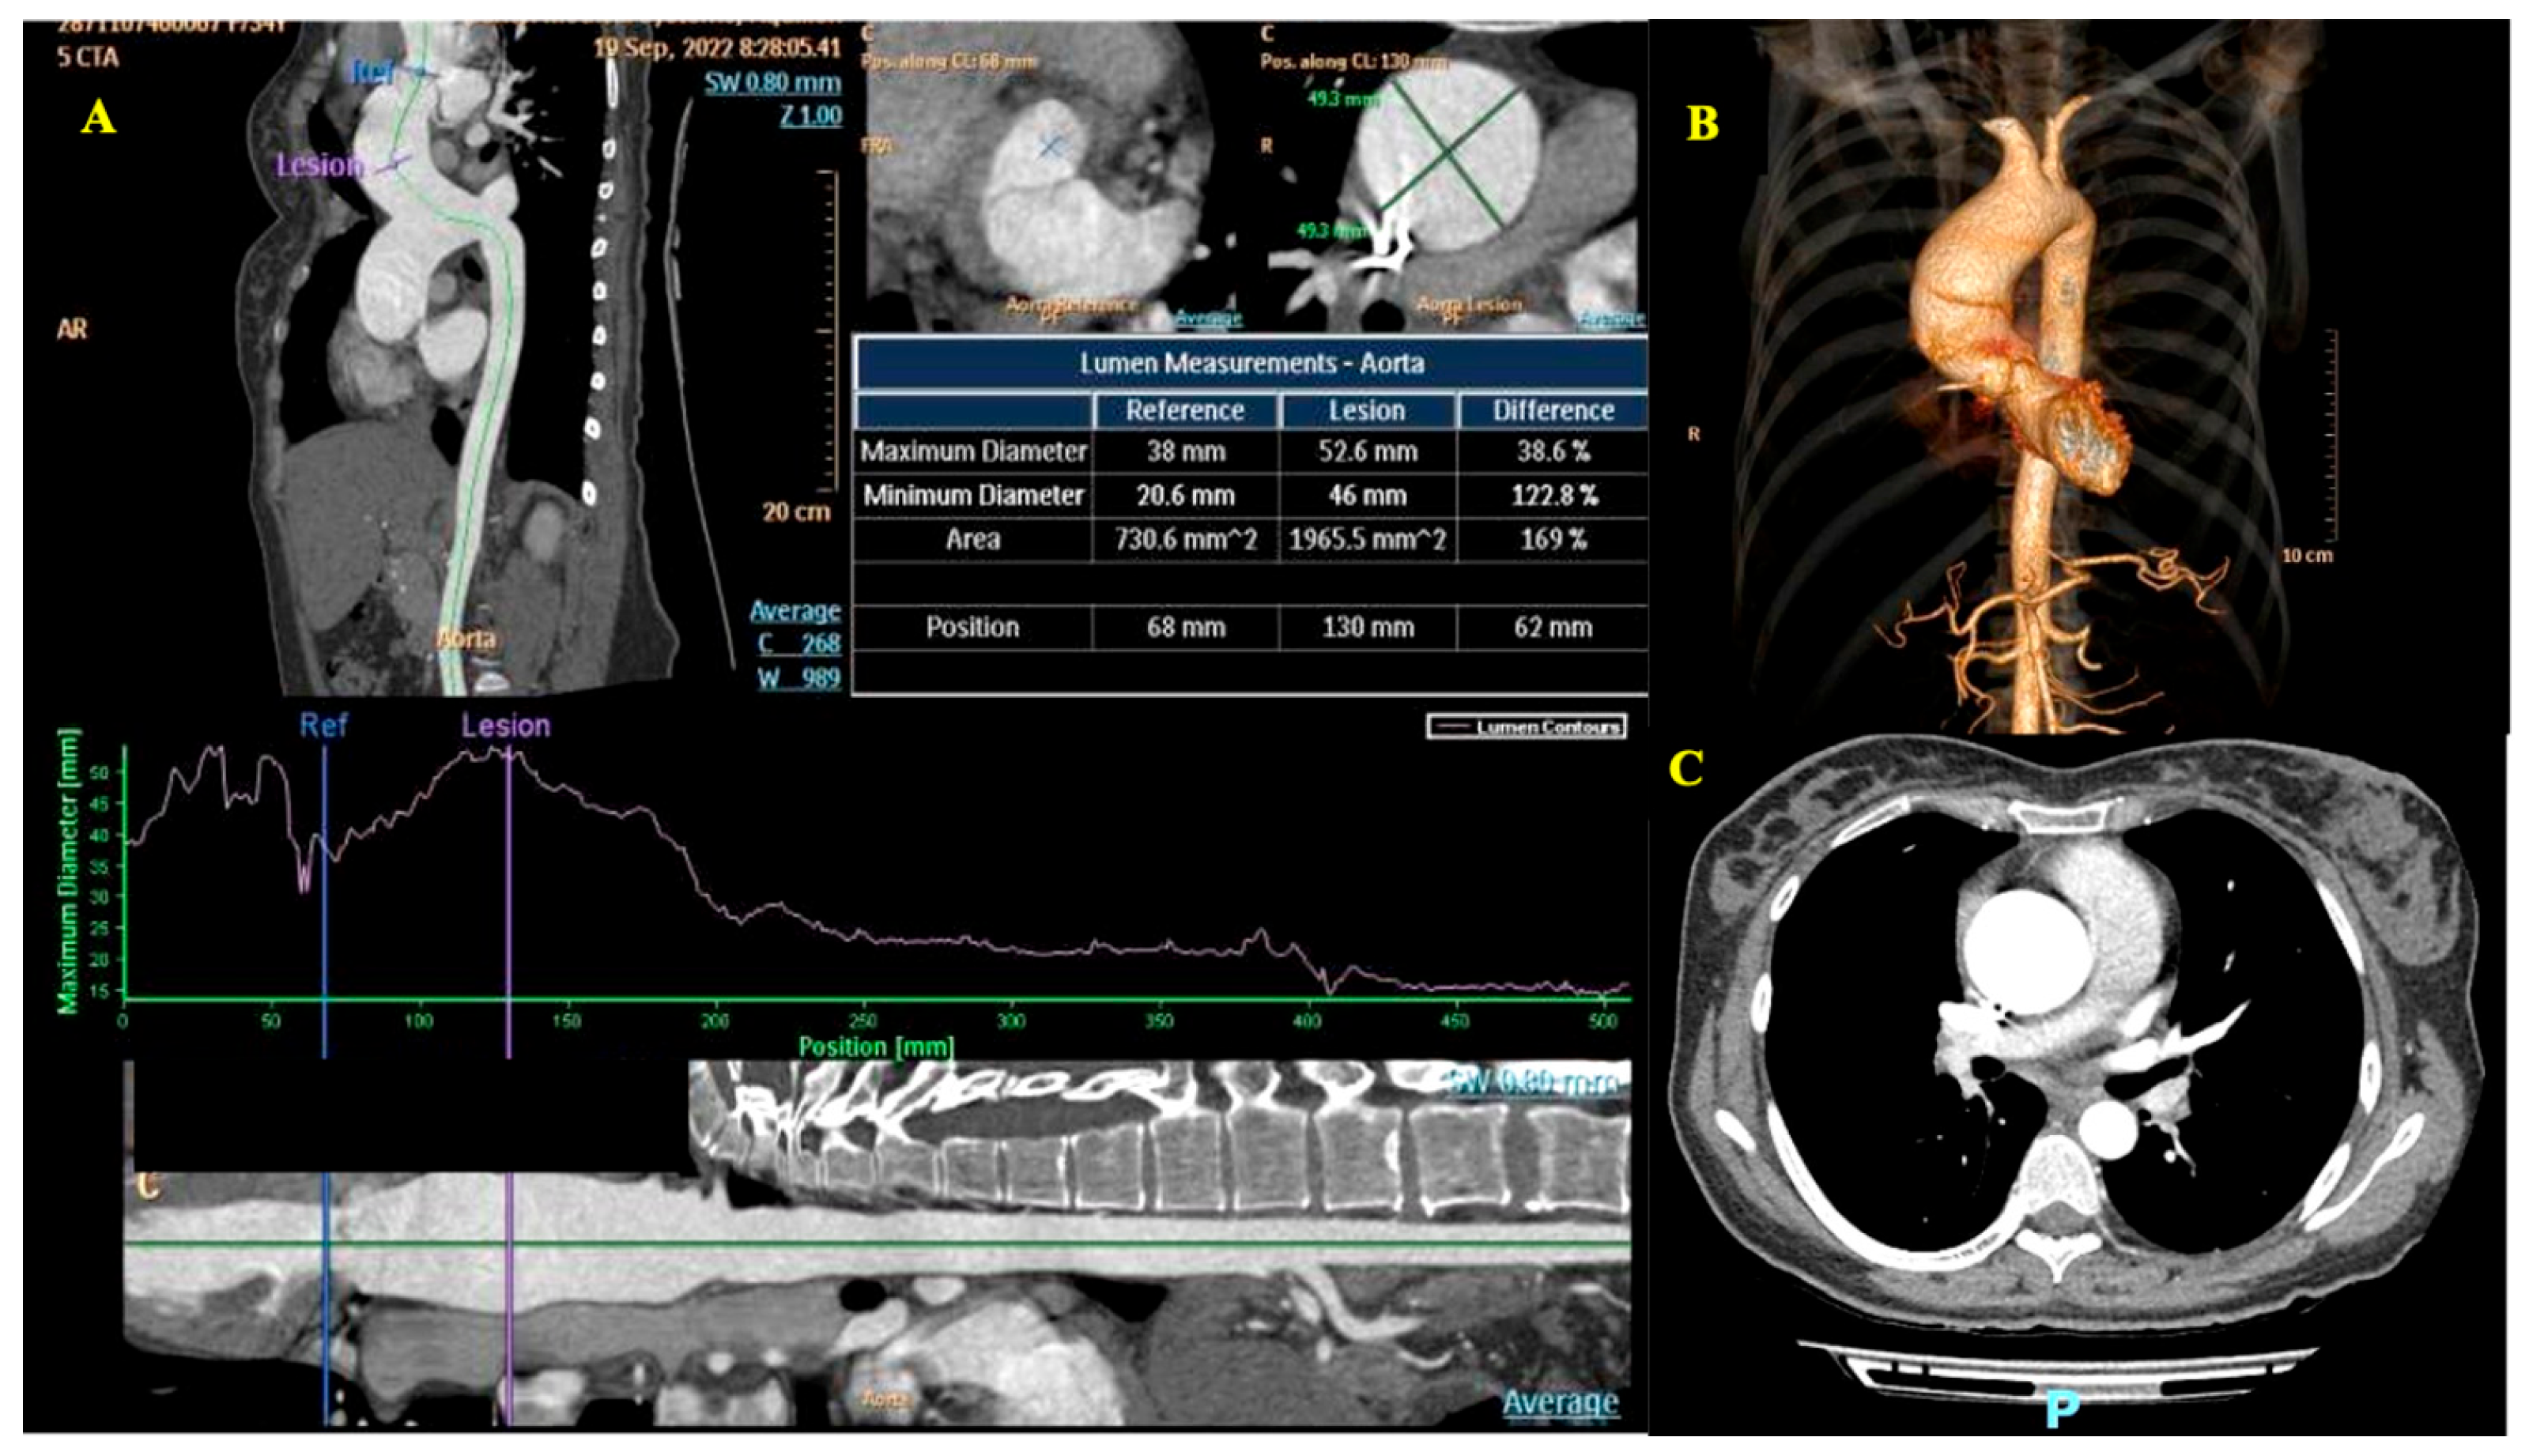

- Aortic balloon valvuloplasty as a bridge to term pregnancy, though this carries risks such as stroke, suboptimal relief, or severe regurgitation that may necessitate urgent transcatheter aortic valve implantation (TAVI).

- (3)

- TAVI during pregnancy, which in our case posed the potential risk of emergent conversion to surgical valve replacement due to the patient’s bicuspid aortic valve. Data from the literature also suggest some technical particularities that may occur in young women, such as femoral arteries with a small diameter and the absence of calcification on the aortic valve annulus, which could make anchoring of the prosthetic valve difficult [20].

- (4)

- Planned surgical valve replacement, which involves a high risk of fetal loss due to the need for cardiopulmonary bypass. The trigger for intervention should always be guided by the patient’s symptomatology during pregnancy [24].